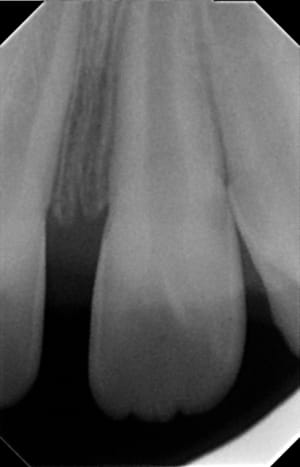

06112015_185217_qb8egl.jpg